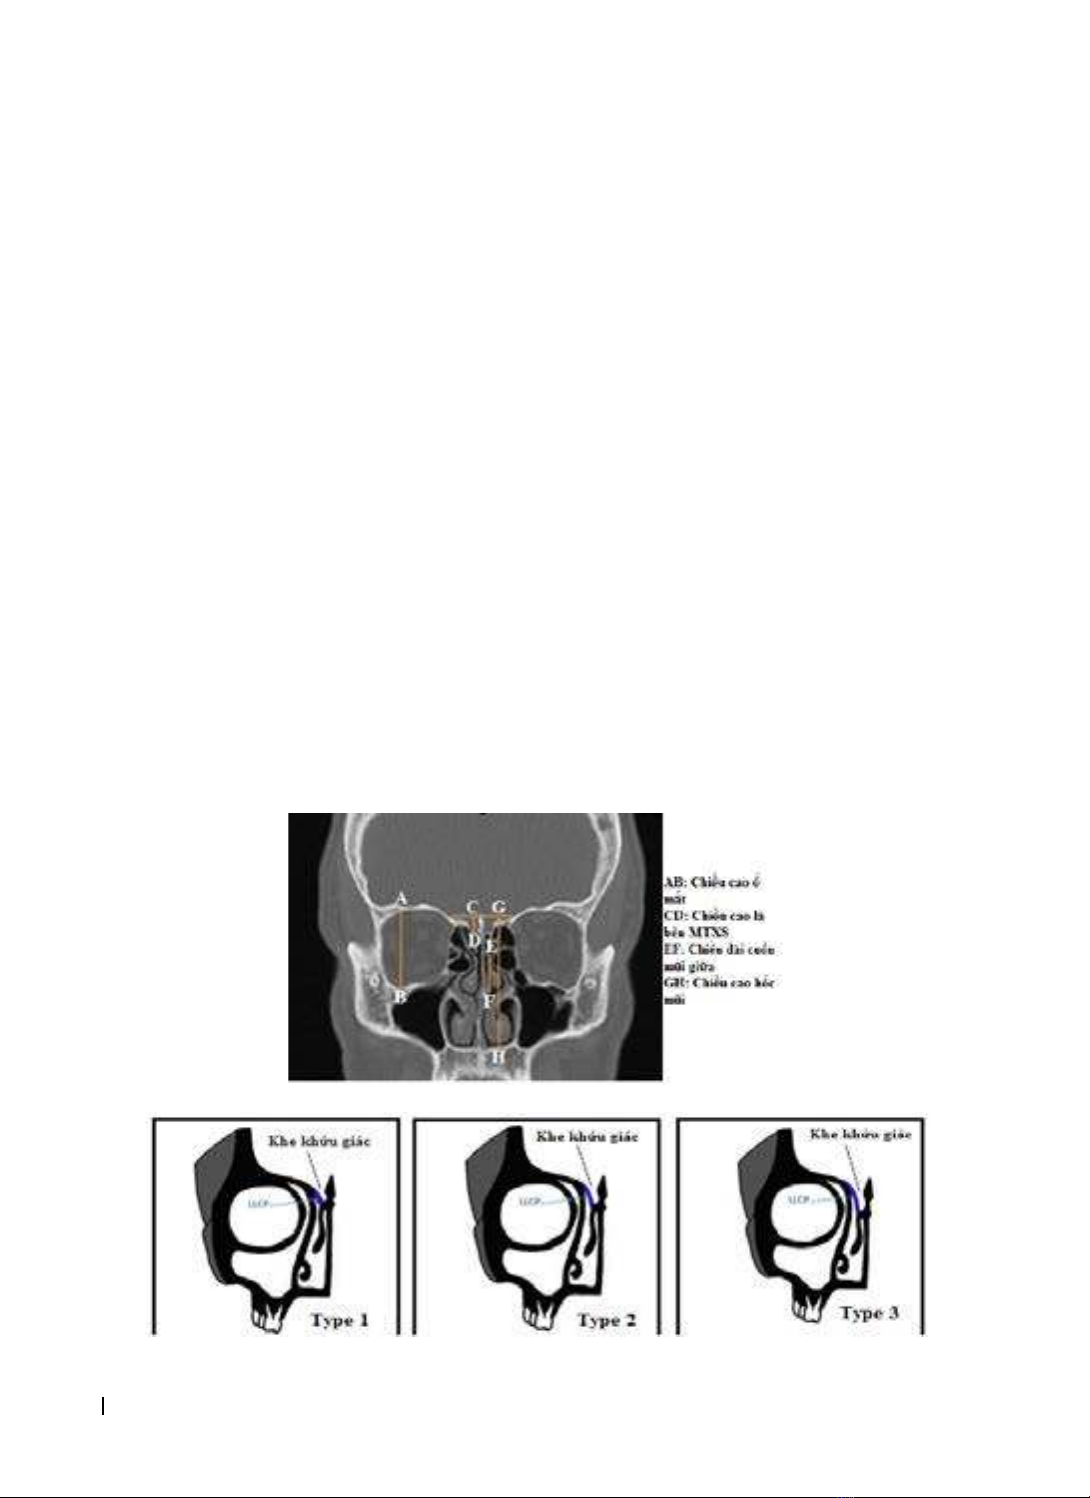

Hình 2.1. Các đo chiều cao lá bên mảnh thủng xương sàng và các cấu trúc lân cận [3]

Hình 2.2. Hình ảnh minh họa 3 type của phân loại Keros [4]